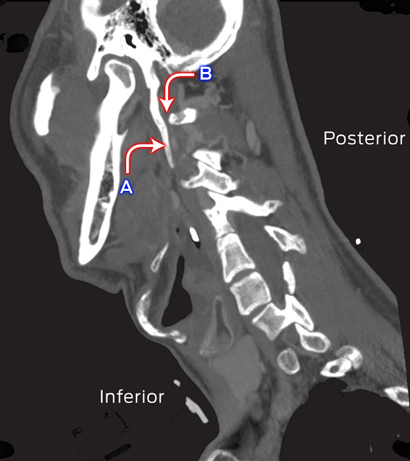

A 38-year-old man presented with influenza A (H1N1) pneumonia complicated by acute respiratory distress syndrome, resulting in an extended intensive care unit stay (37 days). After he was extubated, he was found to have left-side IX, X and XII cranial nerve palsies. Computed tomography of his neck showed bilateral elongated styloid processes (5.0 cm long; Figure), consistent with Eagle syndrome.1 The left styloid process was closely opposed to the transverse process of the first cervical vertebra, causing effacement of the internal jugular vein and compression of the IX, X and XII cranial nerves, which converge in this area. The eponym used to describe concurrent paralyses of the X and XII cranial nerves is Tapia syndrome,2 with prolonged neck flexion potentially contributing to the condition in our case.

Sagittal computed tomography image of the neck of the patient. A: Elongated styloid process (left); B: Area of compression of IX, X and XII cranial nerves.